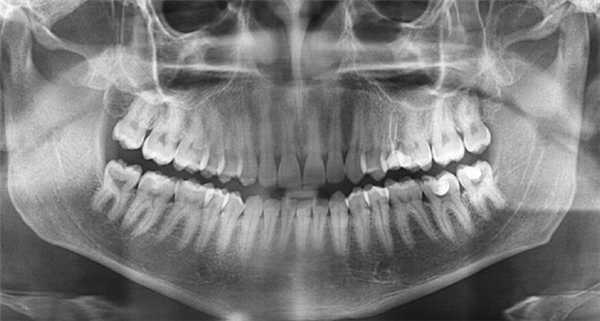

Основной методикой рентгеновского исследования челюстно-лицевой области является ортопантомография (ОПТГ), которая совершенствуется, переходя на цифровой способ получения изображения. На ОПТГ отображается панорамный рентгеновский снимок зубочелюстной системы пациента, на котором видны верхняя и нижняя челюсти, развёрнутые в плоскости, корни, каналы зубов, имеющиеся имплантаты, ортопедические конструкции, пломбы, а также пародонтальные щели, гайморовы пазухи, носовые

ходы, височно-нижнечелюстные суставы, нижнечелюстной канал.

Методика оправдана для предварительных скрининговых исследований широких масс населения, поэтому активно используется при диспансеризации. Ортопантомография превосходит стандартные рентгеновские снимки и позволяет дифференцировать кисты одонтогенного и риногенного происхождения, оценивать окружающие структуры лицевого отдела головы. Однако ОПТГ имеет ряд ограничений — изображение является плоскостным, что не дает возможности оценить распространение кистозного процесса и состояние окружающих структур, а также не в полной мере дает информацию о состоянии корневых каналов.

На основании панорамных снимков диагностируют кариес и его осложнения, кисты разных типов, новообразования, повреждения челюстных костей и зубов, воспалительные и системные поражения. У детей хорошо определяется состояние и положение зачатков зубов.

5. Ортопантомография

Панорамная зонография, или, как ее чаще называют, ортопантомография, явилась своего рода революцией в рентгенологии челюстно-лицевой области и не имеет себе равных по ряду показателей (обзор большого отдела лицевого черепа в идентичных условиях, минимальная лучевая нагрузка, малые затраты времени на исследование).

Панорамная зонография позволяет получить плоское изображение изогнутых поверхностей объемных областей, для чего используют вращение рентгеновской трубки и кассеты.

Преимуществом ортопантомографии является возможность демонстрировать межчелюстные контакты, оценивать Результаты воздействия межчелюстной нагрузки по состоянию замыкающих пластинок лунок и определять ширину периодонтальных путей.

Ортопантомограммы демонстрируют взаимоотношения зубов верхнего ряда с дном верхнечелюстных пазух и позволяют выявить в нижних отделах пазух патологические изменения одонтогенного генеза.

Особенно важно использовать ортопантомографию в детской стоматологии, где она не имеет конкурентов в связи с низкими дозами облучения и большим объемом получаемой информации. В детской практике ортопантомография помогает диагностировать переломы, опухоли, остеомиелит, кариес, периодонтиты, кисты, определять особенности прорезывания зубов и положение зачатков.